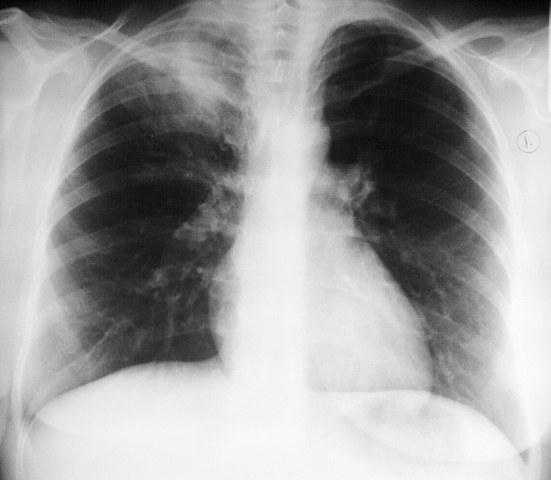

Женщина 32 года; месяц как кашляет. Повышения температутры тела не отмечала. Изначально выполнили рентгенографию. Что делать дальше?

Ок, мы определились с дифференциальным рядом при такой рентгенологической картине (Затемнение верхених сегментов правого лёгкого, S2). Какую рекоммендацию Вы бы дали такому пациенту? Что будем делать дальше?

Далее рекомендуем лабораторные исследования, КТ легких.

KT

Давайте определимся, для начала обозначим какие КТ признаки мы видим на представленных сканах. И главное это не перечисление вариантов диагнозов (если нет однозначного варианта); а определить что надо сделать следующим этапом для достижения окончательного диагноза.

Вполне адекватная тактика. КТ контроль через 3-4 недели после антибактериальной терапии, совершенно правильно.

В данном случае, пульмонолог решил пойти на бронхоскопию; был забор материала. Лабараторный анализ (ПЦР) выявил положительную реакцию на туберкулёз.